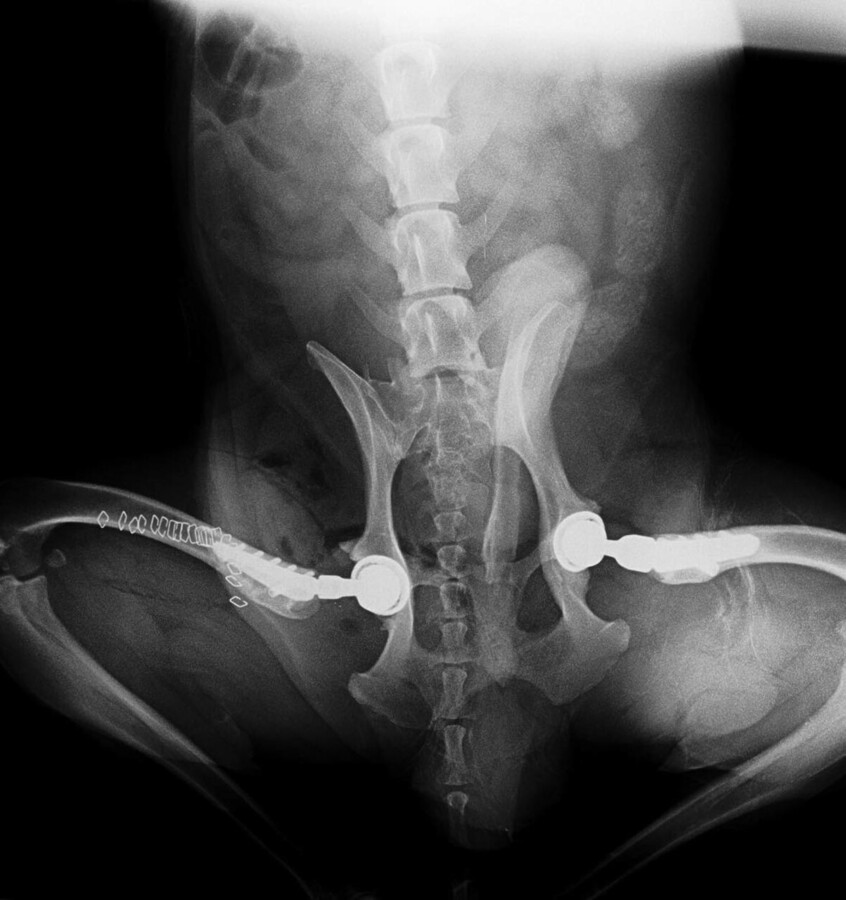

Endoprotezoplastyka w leczeniu chorób stawów

to zaawansowana procedura ortopedyczna polegająca na zastąpieniu uszkodzonego stawu specjalistycznym implantem. Zabieg wykonywany jest u psów z ciężkimi chorobami stawów, które powodują przewlekły ból oraz znaczne ograniczenie ruchomości.

Celem operacji jest odtworzenie prawidłowej biomechaniki stawu, zniesienie bólu oraz przywrócenie zwierzęciu komfortu ruchu. W wielu przypadkach endoprotezoplastyka pozwala psom wrócić do normalnej aktywności, nawet przy zaawansowanych zmianach zwyrodnieniowych.

Najczęściej wykonywaną procedurą w ortopedii weterynaryjnej jest całkowita wymiana stawu biodrowego, jednak implanty mogą być stosowane również w innych stawach.

Wymiana stawu biodrowego

To najczęstsze zastosowanie endoprotez w weterynarii. Zabieg polega na zastąpieniu głowy kości udowej oraz panewki stawu biodrowego implantem. Procedura wykonywana jest przede wszystkim u psów z ciężką dysplazją stawu biodrowego lub zaawansowanymi zmianami zwyrodnieniowymi.

Podczas operacji chirurg usuwa uszkodzone elementy stawu, a następnie wprowadza implant ortopedyczny, który odtwarza jego funkcję. Proteza składa się zwykle z kilku elementów wykonanych z materiałów biokompatybilnych, takich jak tytan czy specjalne tworzywa medyczne.

Implant pozwala na odtworzenie prawidłowego ruchu w stawie oraz stabilizację jego struktur.